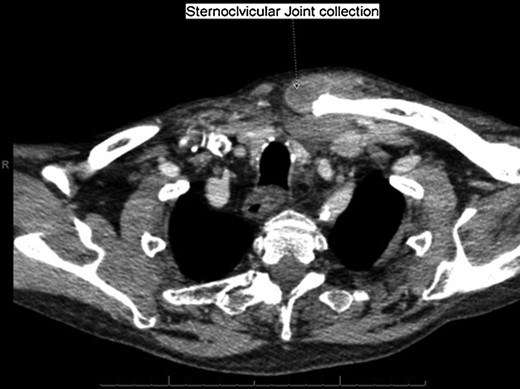

With a working differential of parapharyngeal space infection and possible malignancy, the patient was referred for a computed tomography (CT) scan of the neck and thorax with contrast. The patient was also started empirically on intravenous co-amoxiclav as treatment for neck space collection. CT imaging, performed 24 h after admission, revealed no evidence of malignancy or indeed any paraphayrngeal space collection. Few small lymph nodes were noted on the left side of the neck, but were deemed to be reactive in nature, and left vocal cord palsy was evident (Fig. 1). The key finding was that of a left sternoclavicular joint collection and closely associated superficial anterior chest wall, soft tissue swelling and oedema (Fig. 2). This inflammatory process was also noted deep to the manubrium and sternum and extending somewhat into the mediastinum with evident enlarged mediastinal lymph nodes (Fig. 3). The CT findings were in keeping with SSA with associated superficial and deep tissue inflammation and oedema. With no other cause found, the vocal cord palsy was attributed to the inflammation within the mediastinum, which in turn was caused by superficial burn from hot water bottle use.

Computed tomography. A 67-year-old male with SSA. Findings: soft tissue oedema of the chest seen retrosternally (marker A) and superficially on the left anterior chest (marker B) as well as evidence of mediastinal lymph node enlargement. Technique: contrast-enhanced axial CT of the neck and thorax.